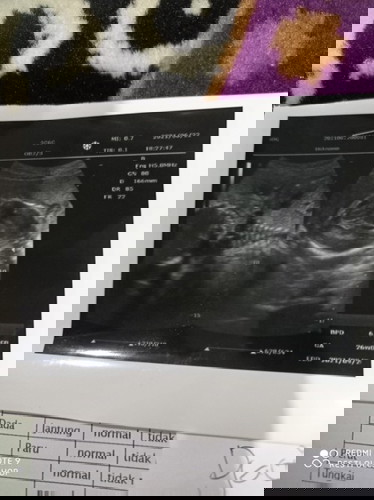

plasenta (ari ari di bawah )usia kandungan 26 week apakah bahaya atau tidak ?

setau saya, seharusnya ari2 tidak boleh menutup i jalan lahir bun...